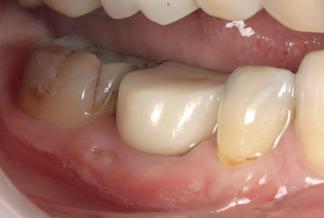

Case 1: Anterior tooth restoration with composite